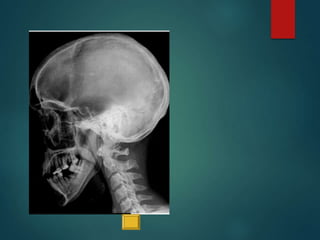

Este documento proporciona instrucciones para realizar diferentes proyecciones radiográficas del cráneo, incluyendo las proyecciones anteroposterior (AP), submentovertex (SMV), parietoorbitaria y transorbitaria de Guillen. Describe los ángulos y posiciones requeridos para cada proyección y las estructuras óseas que deberían ser visibles en cada imagen resultante.